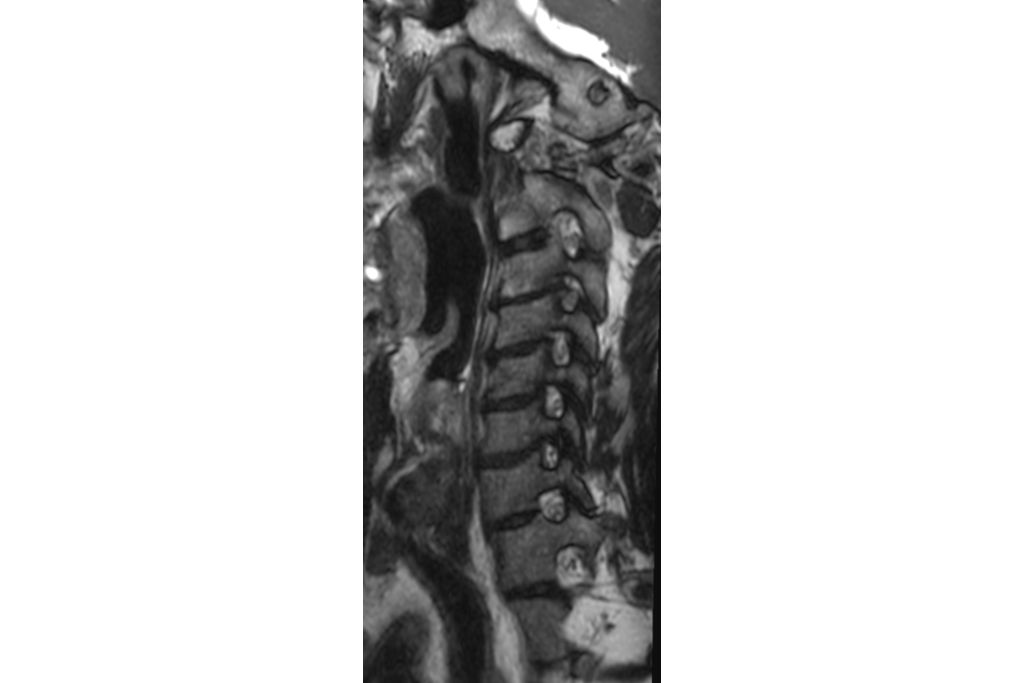

• Sagittal 3D SpineVIEW T2w TSE - Oblique Reformats

Sagittal 3D SpineVIEW T2w TSE - Oblique Reformats

• Sagittal 3D SpineVIEW T2w TSE

Sagittal 3D SpineVIEW T2w TSE